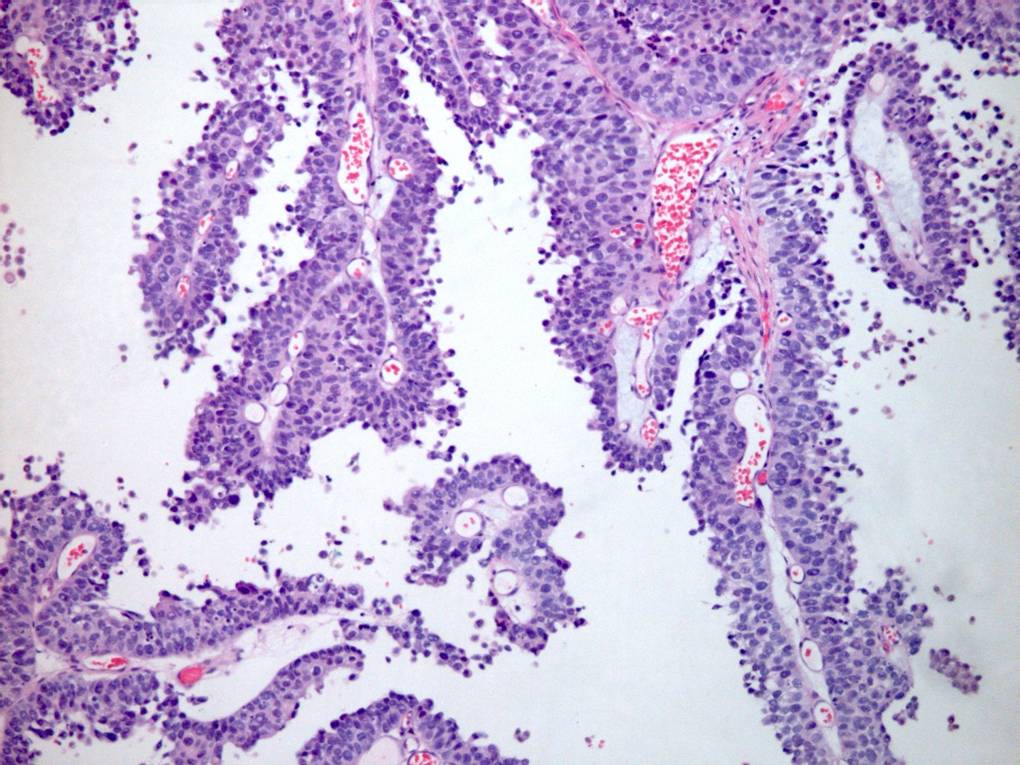

Consensus grade: High-grade papillary urothelial carcinoma (HG-PUC)

Case description (by case creator):

65 year old male. From TURBT. Diagnosis illustrated = high grade papillary urothelial carcinoma